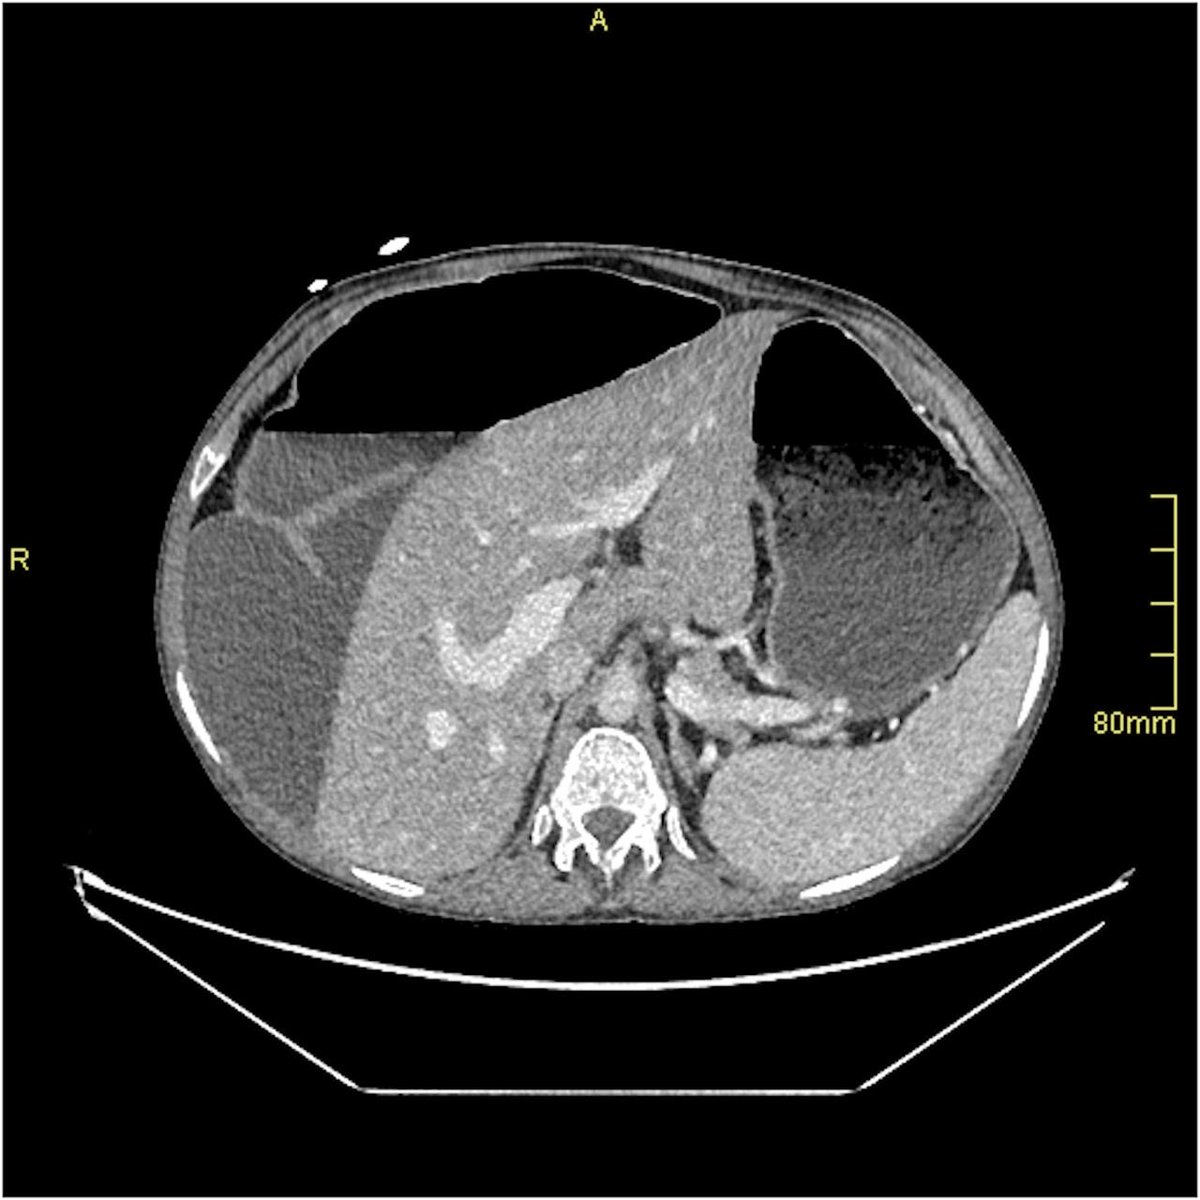

🚨 NEW in Frontline Gastroenterology! A 23-year-old on lifelong parenteral nutrition had abnormal liver tests, but FibroScan and ultrasound kept 'failing'. Cross-sectional imaging was organised that showed the reason💡 . What does the CT show and how did the team complete

Abnormal liver blood tests in patients on long term parenteral nutrition are common and can be challenging to understand. Prospective studies exploring the role of NITs are currently lacking. Have a look at our unusual case in ⁦⁦@FrontGastro_BMJ https://t.co/MHmqtPfHEb